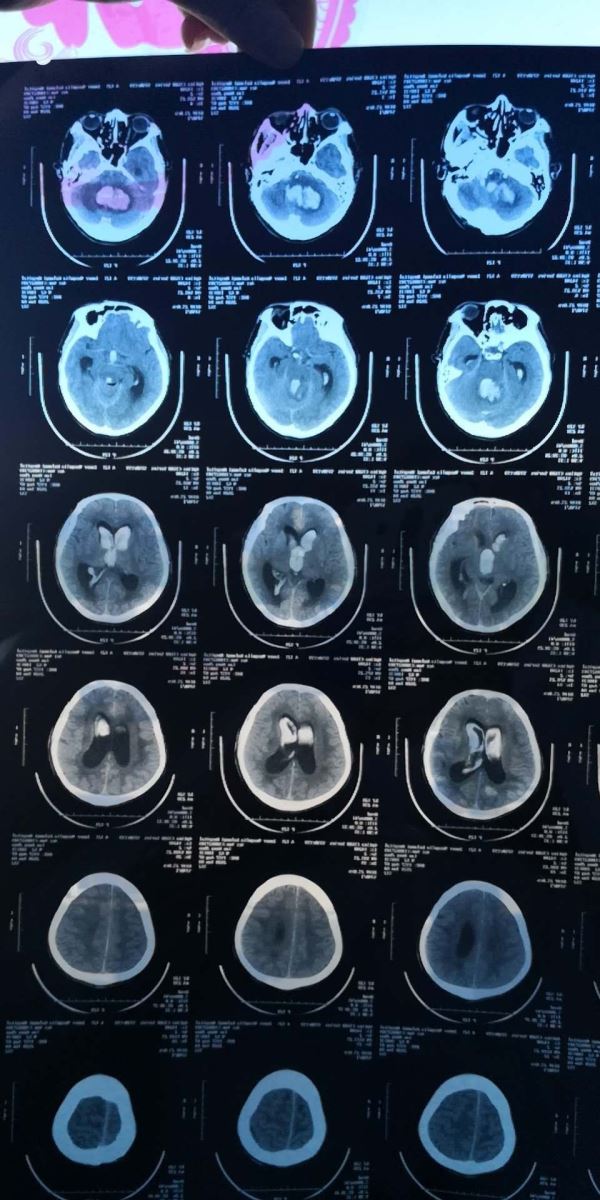

老年男性患者,既往诊断“右侧小脑血管畸形”,未进行系统诊治。晨起无诱因突发昏迷,频繁呕吐,为胃内容物,无咖啡样物。患者家属将患者急送至库伦旗医院就诊,急诊检查头部CT考虑右侧小脑出血、梗阻性脑积水,库伦旗医院给予患者气管插管抢救,并立即启动对口帮扶医院协助,与我院东院区神经外科联系后,由120护送至我院就诊。来院后,患者出现呼吸衰竭,急诊科立即启动卒中中心绿色通道,行脑室外引流抢救手术,CT室行CT脑血管三维成像检查(CTA)。检查结果提示:枕大孔区硬膜动静脉瘘。神经外科团队紧急讨论,充分论证疾病危重程度并制定治疗方案,与患者家属紧急沟通,在取得患者家属同意后决定行后颅凹开颅右侧小脑血肿清除、枕大孔区硬膜动静脉瘘切除术手术抢救治疗。在东院区手麻科主任医师陈铁军的积极配合下,由主任医师张永哲主刀,主任医师赵程欣和医生李兵桥的协助下,成功完成本例手术。

硬脑膜动静脉瘘(DuralArteriovenous Fistula,DAVF)是指发生在硬脑膜、大脑镰、小脑幕和静脉窦上的异常动静脉分流,占颅内血管畸形的5%~15%。由颈外、内动脉或椎动脉的脑膜支供血,通过异常的短路引流入相邻的静脉窦并可逆流至软脑膜静脉。任何年龄段均可发病,但以40~60岁最多。横窦区以女性居多,前颅窝底以男性居多,其他部位男女比例接近。DAVF的临床表现不一,从无症状的神经影像学表现到致死性脑出血,都可能出现,瘘口的位置和等级是影响表现的关键因素。手术治疗DAVF的指证包括:需急诊清除颅内血肿的患者,多支供血动脉,其他技术不能到达供血动脉或供血动脉参与或与重要的脑神经比邻。枕大孔区DAVF的临床表现、预后、治疗方式取决于其血管构筑模式,特别是病灶部位和静脉引流方式,外科手术一般能找到瘘口并能将其完全切除。